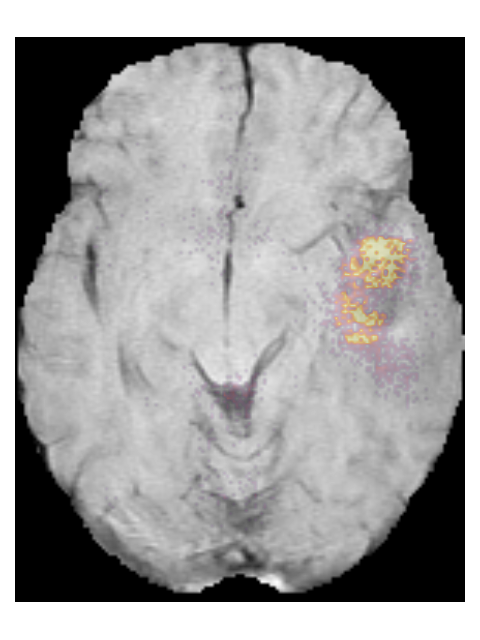

To provide insight into the behavior of our model we created saliency maps, which show which parts of the scans contributed the most to the prediction. These saliency maps are shown in Figure 6 for two example patients from the test set. It can be seen that for the LGG the network focused on a bright rim in the T2w-FLAIR scan, whereas for the HGG it focused on the enhancement in the post-contrast T1w scan. To aid further interpretation, we provide visualizations of selected filter outputs in the network in Appendix D, which also show that the network focuses on the tumor, and these filters seem to recognize specific imaging features such as the contrast enhancement and T2w-FLAIR brightness.

To demonstrate the automatic segmentations made by our method, we randomly selected five patients from both the TCGA-LGG and the TCGA-GBM dataset. The scans and segmentations of the five patients from the TCGA-LGG dataset and the TCGA-GBM dataset are shown in Figures 12 and 14, respectively. The DICE score, Hausdorff distance, and volumetric similarity coefficient for these patients are given in Table 7. The method seems to mostly focus on the hyperintensities of the T2w-FLAIR scan. Despite the registrations issues that can be seen for the T2w scan in Figure 14(d) the tumor was still properly segmented, demonstrating the robustness of our method.